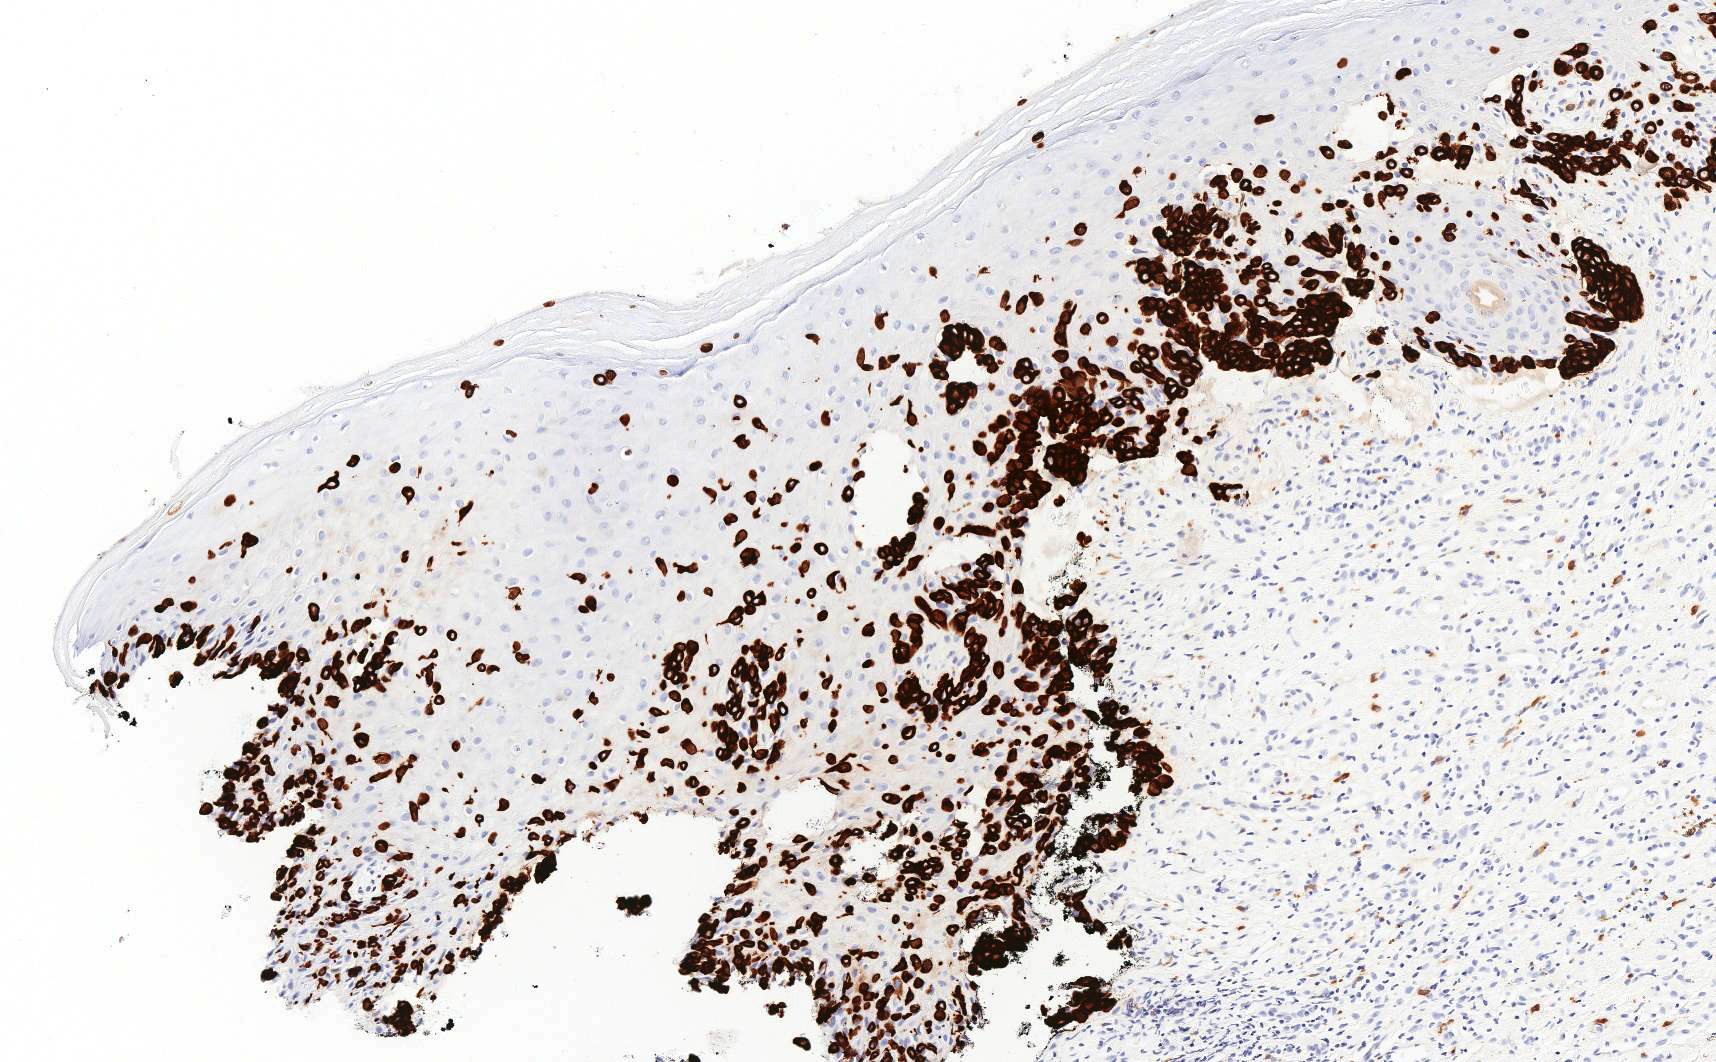

- In primary Paget disease, neoplastic cells are consistently strongly positive for CK7

Microscopic (histologic) images

Contributed by Priya Nagarajan, M.D., Ph.D. and Lucy Ma, M.D.

- Primary and secondary Paget disease: CAM 5.2, EMA, CEA, mucicarmine, periodic acid-Schiff (PAS)

- Primary Paget disease: CK7, GATA3, GCDFP-15, androgen receptor, p16 (weak to moderate) (Am J Clin Pathol 2000;113:572)

- Comment: On immunostains, the neoplastic cells are strongly positive for CK7 and CAM 5.2 and negative for SOX10, supporting the diagnosis.